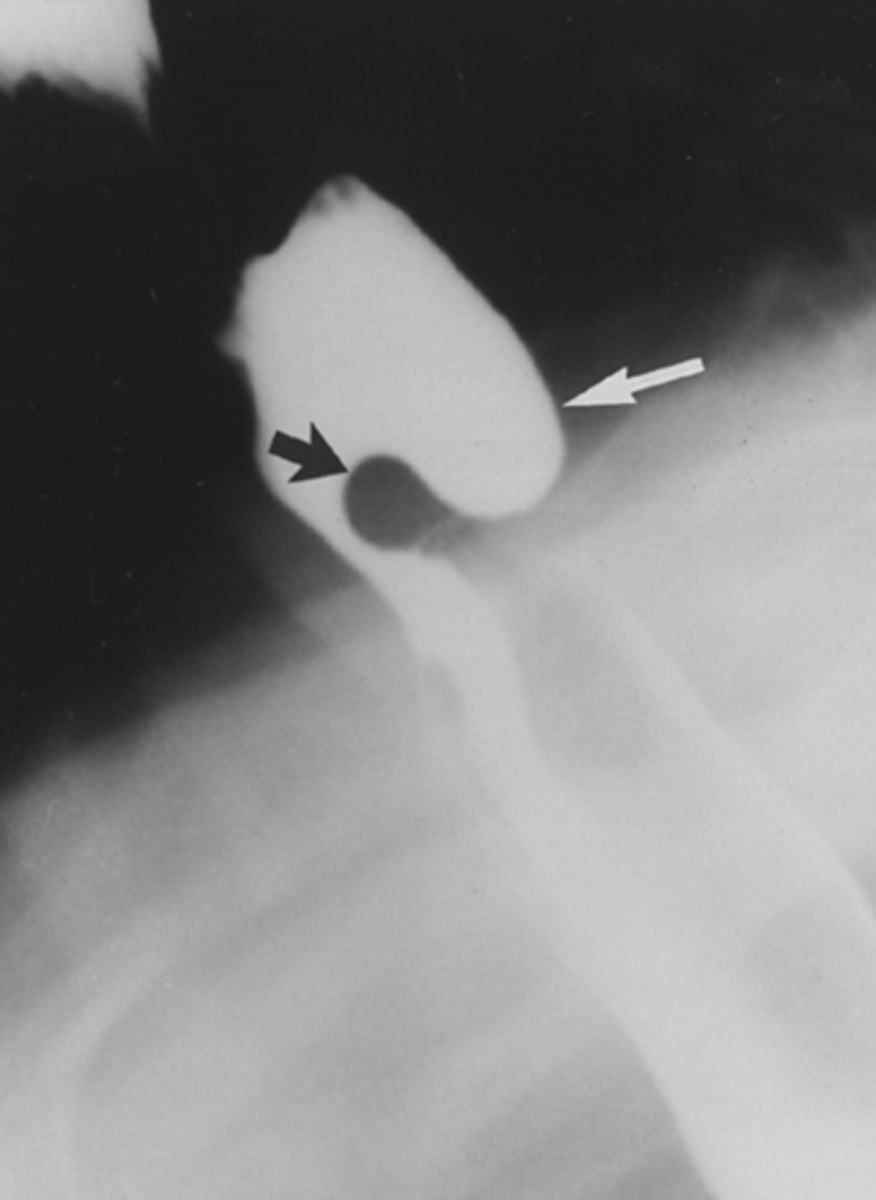

Cricopharyngeal achalasia/Zenker's diverticulum

rare clinical entity in which upper esophageal sphincter (cricopharyngeus) does not open adequately during swallowing leading to dysphagia.

Diverticulum of the mucosa of the pharynx just above the cricopharyngeal muscle.

Zenker's diverticulum